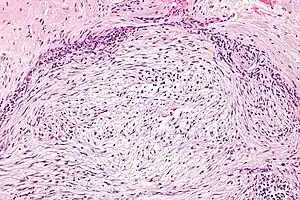

| Micrograph of nodular fasciitis showing the haphazard arrangement of cells (tissue culture-like pattern). H&E stain. | |

The microscopic histopathology of hematoxylin and eosin stained nodular fasciitis tumors (see above and three below figures) consists of spindle-shaped myofibroblastic cells (i.e. cells with features of smooth muscle cells and fibroblasts.).[9] These cells are in a myxoid (i.e. more blue or purple compared to normal connective tissue because of excessive uptake of the hematoxylin stain) or a collagenous (high content of collagen fibers) tissue background. The neoplastic myofibroblasts are arranged in whorls and/or short bundles. These cells may show high rates of replicating as judged by their mitotic index but these mitoses are normal in appearance. The tumor tissues often contain red blood cells, lymphocytes and giant osteoclast-like giant cells and may contain sites of bone-like tissue.[11] NF is sometimes classified into three subtypes based on its predominant histopathological pattern: myxoid or reactive (type I), cellular (type II), and fibrous (type III).[5] These patterns appear related to the duration of the lesion with the myxoid variant tending to have the shortest duration and the cellular and fibrous variants tending to have progressively longer durations.[15]Immunohistochemical analyses indicate that the cells in NF usually express smooth muscle actin, muscle specific actin, and vimentin proteins but generally do not express CD34, S-100 protein, desmin, trypsin, factor VIII, F4/80 (also termed macrophage-specific antigen), or HLA-DR1 proteins.[11] Uncommonly, the cells in NF tumors also express the CD68 (a histiocyte-specific marker) protein.[5]